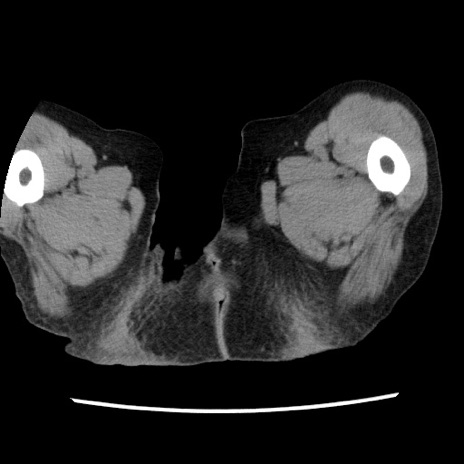

症例1(横断像)

症例

【症例】80歳代女性

【主訴】腹痛

【現病歴】8時間前から腹痛あり来院。

【既往歴】糖尿病、脂質異常症、子宮体癌にて子宮全摘術

【身体所見】意識清明・会話良好だが腹痛で苦悶様、全腹部にわたって反跳痛と圧痛あり

【データ】WBC 13600、CRP 0.14、LDH 224、CK 90